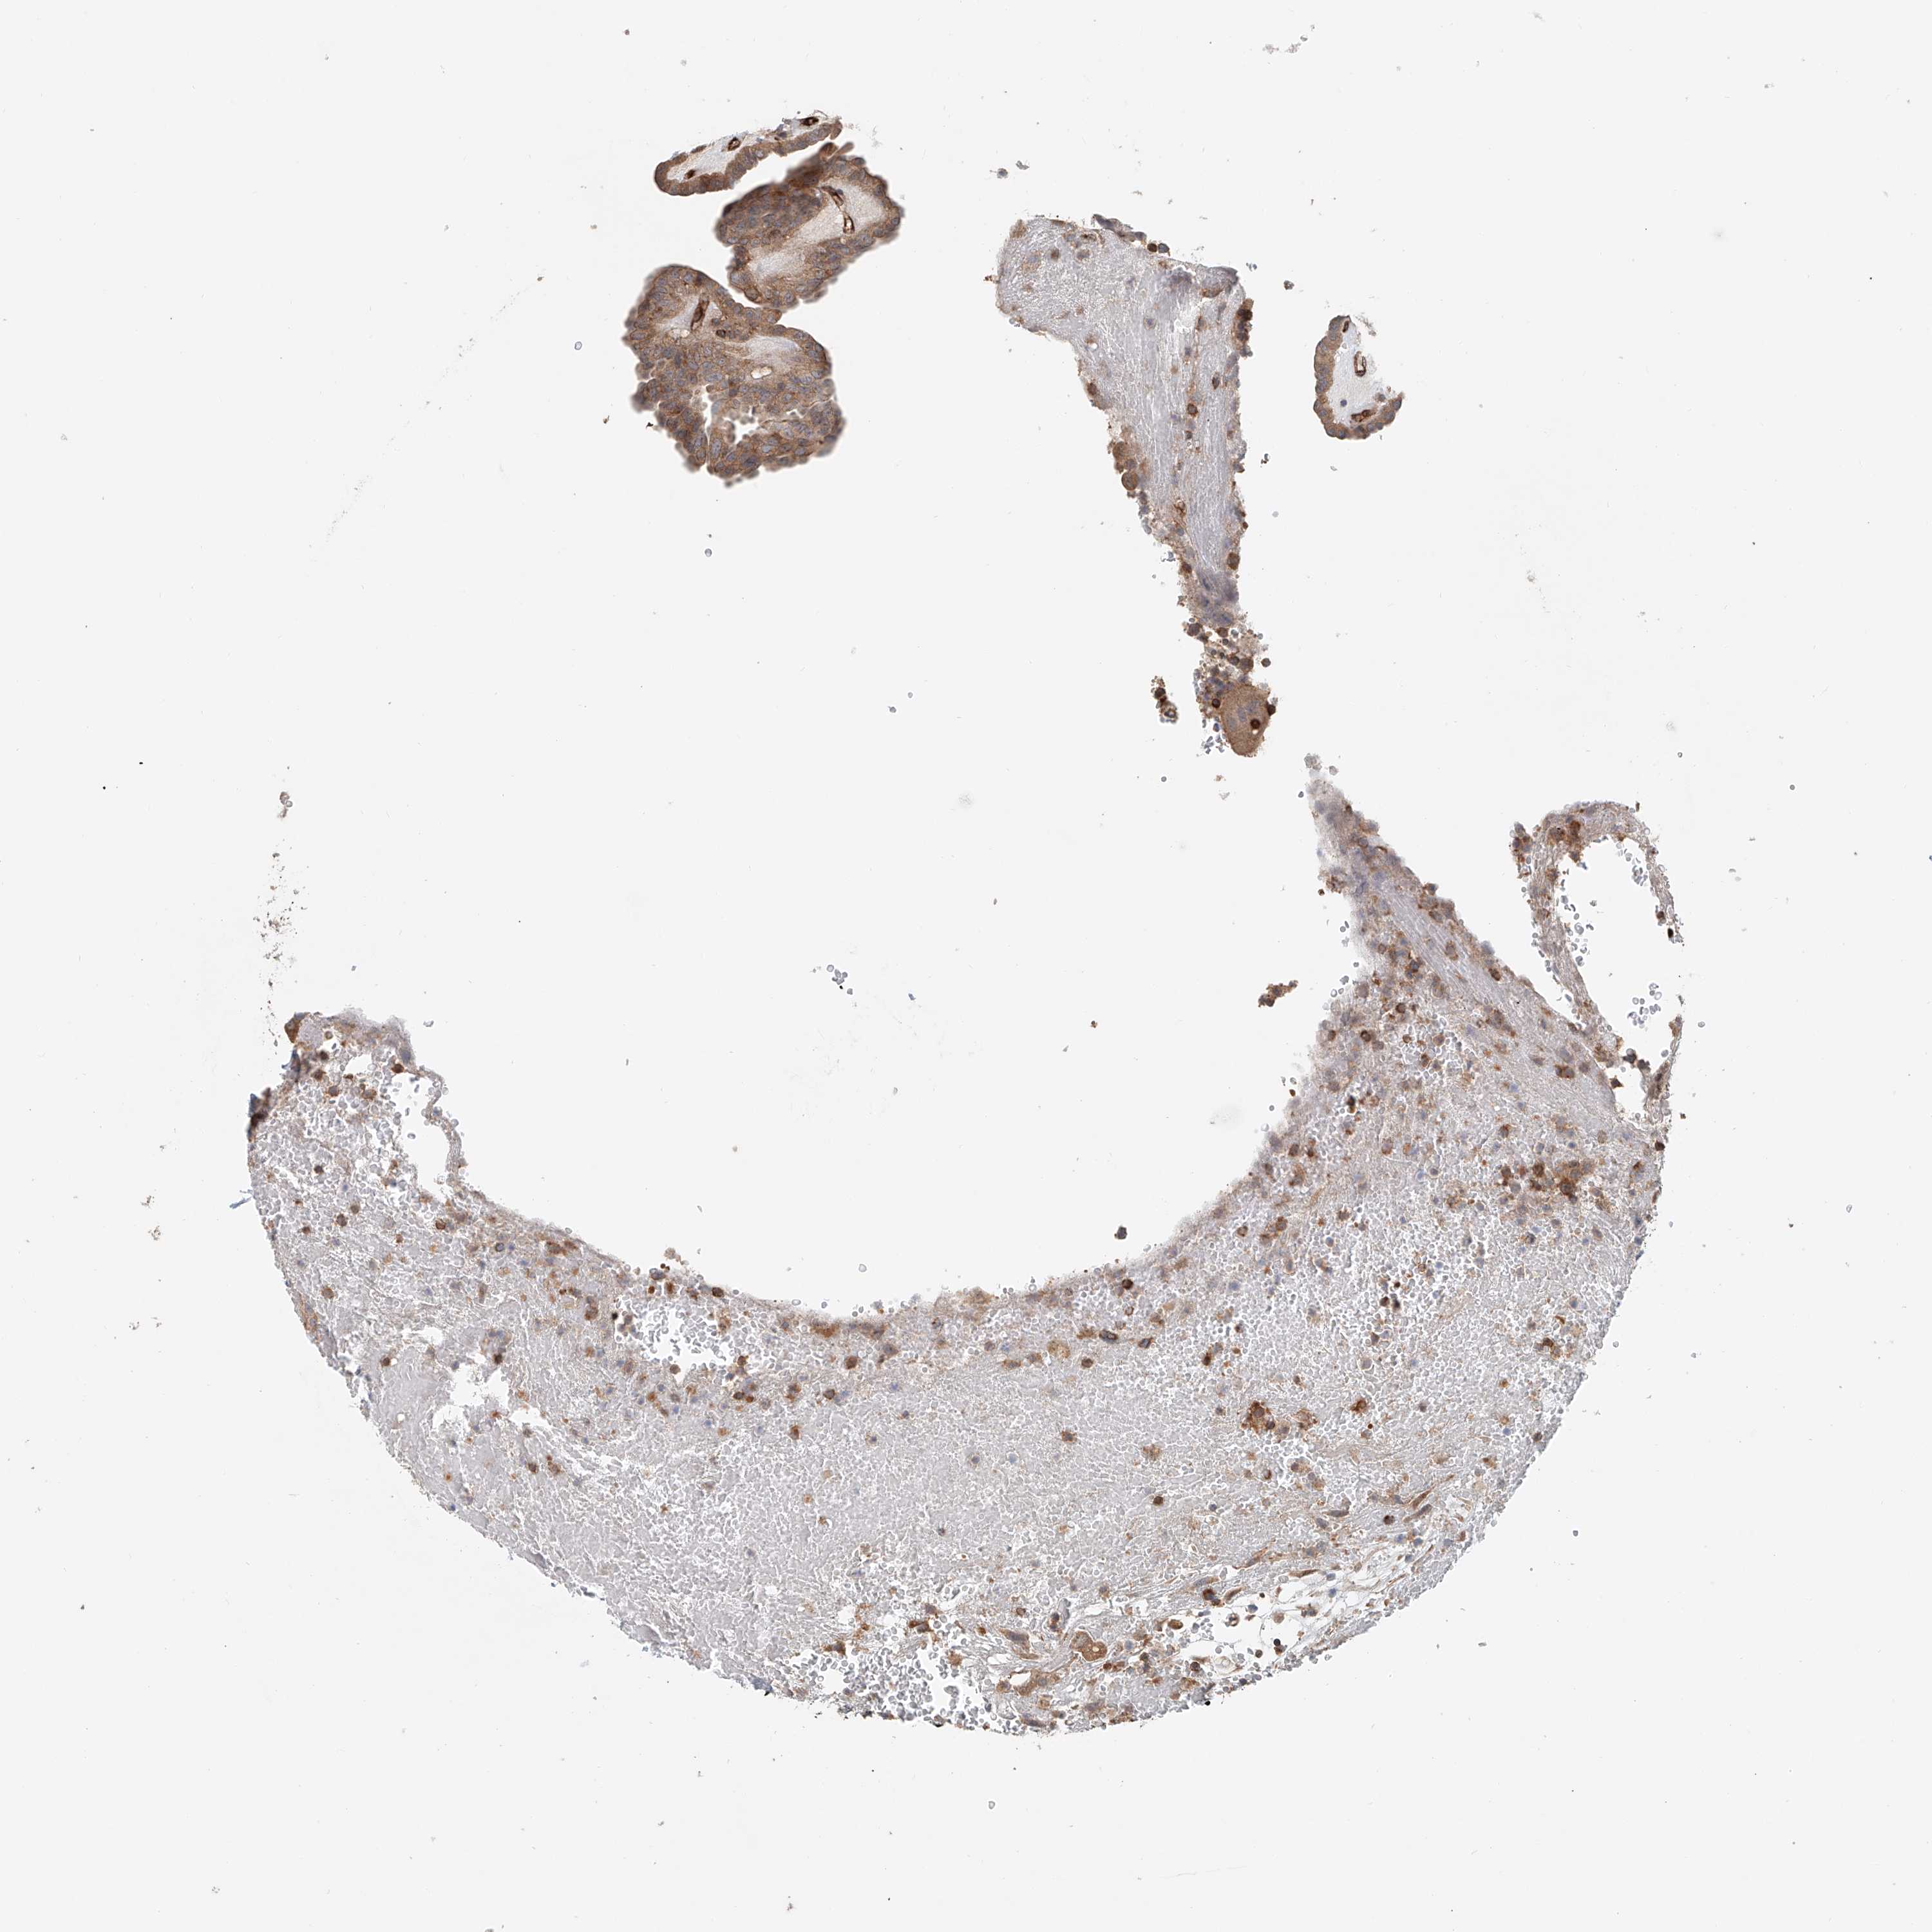

THYROID CANCER - Protein expressioni

A mouse-over function shows sample information and annotation data. Click on an image to view it in a full screen mode. Samples can be filtered based on level of antibody staining by selecting one or several of the following categories: high, medium, low and not detected. The assay and annotation is described here.

Note that samples used for immunohistochemistry by the Human Protein Atlas do not correspond to samples in the TCGA dataset.

Antibody stainingi

Antibody staining in the annotated cell types in the current human tissue is reported as not detected, low, medium, or high, based on conventional immunohistochemistry profiling in selected tissues. This score is based on the combination of the staining intensity and fraction of stained cells.

Each image is clickable and will lead to virtual microscopy that enables deeper exploration of all samples and also displays staining intensity scores, fraction scores and subcellular localization as well as patient and tissue information for each sample.

Antibody HPA031106

Antibody HPA031107

Staining

High

Medium

Low

Not detected

Intensity

Strong

Moderate

Weak

Negative

Quantity

>75%

75%-25%

<25%

None

Location

Nuclear

Cytoplasmic/membranous

Cytoplasmic/membranous,nuclear

Papillary adenocarcinoma, NOS

Follicular adenoma carcinoma, NOS